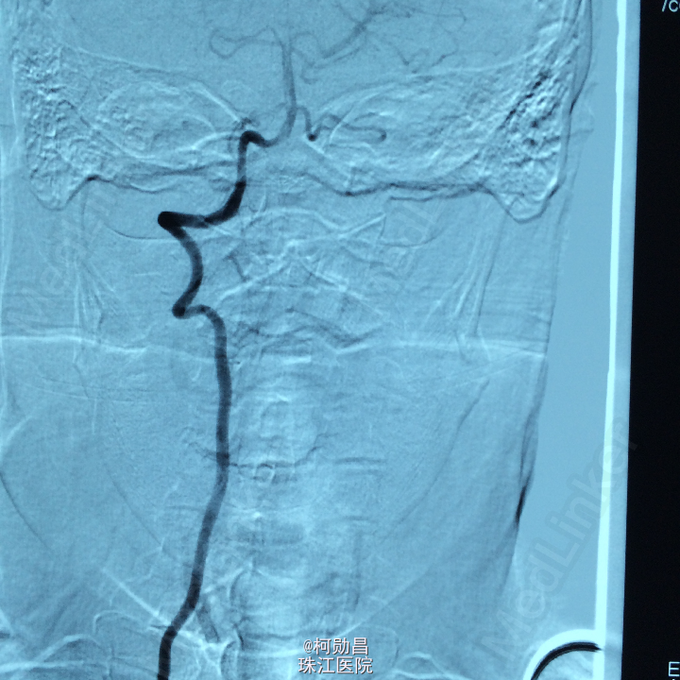

查体:痉挛性截瘫,肌力 4/5 级,马鞍区感觉减退,肛门括约肌张力下降, 腱反射活跃。 辅助检查:腰椎穿刺脑脊液检查示脑脊液蛋白 53mg/dL,葡萄糖 59mg/dL,细胞学检查可见成熟的淋巴细胞,寡克隆区带阴性,免疫球蛋白 IgG 指数为 0.58。布氏杆菌、梅毒、脑脊液 / 血清血管紧张素转换酶水平、结核杆菌聚合酶链反应、单纯疱疹病毒、EB 病毒、水痘 - 带状疱疹病毒,包柔螺旋体(莱姆病)血清学检测均为阴性。结合患者的脊髓 MRI 表现,初步诊断为脊髓血管畸形

诊断:硬脊膜动静脉瘘 处理:予全麻下行栓塞治疗,选择予 withn-butyle-2-cyanoacrylate(医用胶)完全闭塞 。